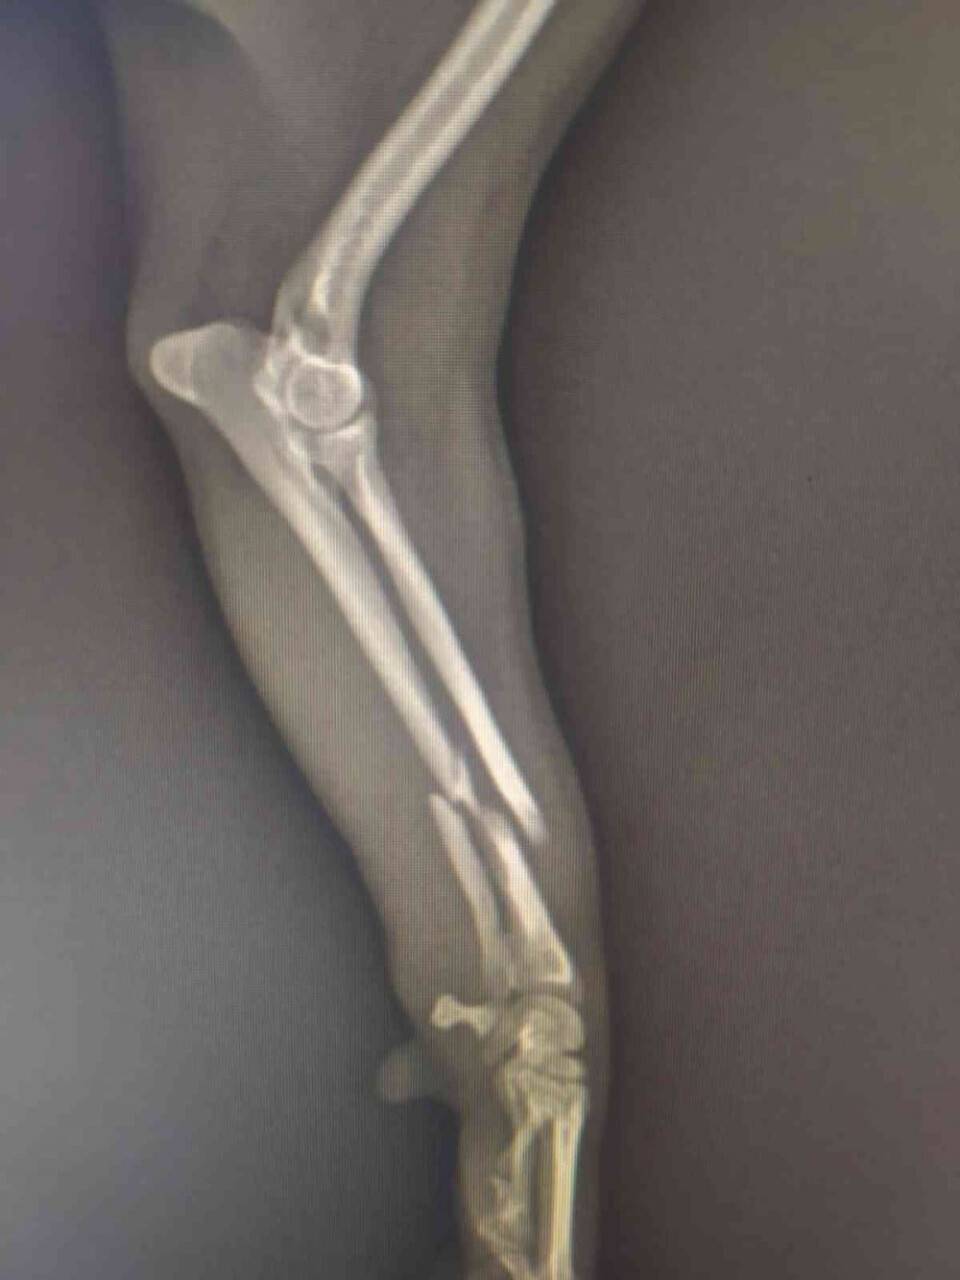

Olay, 2 gün önce Marmaris'te meydana geldi. Edinilen bilgiye göre, doğduğu andan itibaren Gündoğdu çifti ile yaşayan 1 kilo 800 gram ağırlığında 1 yaşındaki Roxie isimli köpek önceki gün evlerinde oyun oynarken koltuktan zıpladığı sırada yere düşünce bir gariplik hisseden aile daha önce aşılarını yaptırdıkları veterineri arayarak durumu anlattı. Veteriner ertesi sabaha randevu verip röntgen çekilmesi gerektiğini belirtince Gündoğdu ailesi köpeklerini alıp kliniğe götürdü. Röntgen sonuçlarında kırık teşhisi konulan köpek ameliyat için hazırlandı. Sabah 10'dan akşam 17.00'a kadar veterinerde bekleyen aileye köpeklerinin telef olduğu belirtildi. Gündoğdu ailesi savcılıkta verdikleri ifadelerinde "Köpeğimizin bacağında kırık tespit ettiklerini ve ameliyat edilmesi gerektiğini söylediler, bizde tamam dedik. Ancak köpeğimiz ameliyata alınmasının üzerinden 3 saat geçti hala içeriden cevap gelmedi. Sorular sorduk, içeri girip kırık beklediğimizden farklı çıktı dediler. Hatta başka bir veteriner cerrah geldi. Yaklaşık 45 dakika içeride kaldı o çıkınca ona sorduk. Bize ben ilaç almaya geldim gelince de biraz lafladık cevabını verdi, gitti. Ameliyatın dördüncü saatinde bir bez içinde veteriner kliniği sahibi veteriner hekim köpeğimizi getirerek "kaybettik" dedi. O an şok olduk ne yapacağımızı bilemedik "neden böyle oldu" diye sorduğumuzda cevap vermediler" dedi.